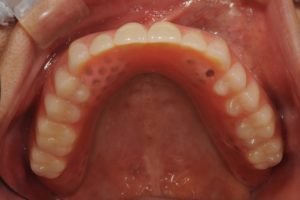

【入れ歯を装着したお口の中】